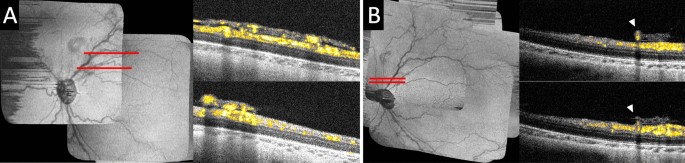

In an eye with aggressive ROP at 36 weeks PMA, extraretinal neovascular tissue was found in the posterior pole and assumed a flatter configuration over a wider surface area (Fig. 4A) compared to typical extraretinal neovascular plaques (Fig. 3). It appeared to be a coalescence of multiple extraretinal neovascular buds just superior to the optic disc. This extraretinal neovascular flow corresponded to what was clinically described as flat neovascularization observed in infants with aggressive ROP. Compared to the extraretinal neovascular plaques in which flow signal was seen in multiple layers stemming from one or few peripheral feeder vessels, flow signal could be seen more diffusely across the extraretinal neovascular tissue, with multiple distinct stems arising from the underlying superficial retinal vasculature.

Optical coherence tomography angiography of extraretinal flat neovascularization in an eye with aggressive retinopathy of prematurity (ROP), and regressed extraretinal neovascularization following intraretinal bevacizumab treatment. (A) In an eye with aggressive ROP at 36 weeks PMA, OCT B-scans with flow overlay near the posterior pole superior to the optic disc along the superotemporal arcade showed vascular flow in the extraretinal neovascular tissue appeared flatter and over a wider retinal surface area compared to the extraretinal neovascular plaques. (B) The same eye was imaged at 47 weeks PMA following bevacizumab treatment at 36 weeks PMA. The preretinal neovascular tissue was regressed and marked reduction of vascular flow within the preretinal tissue. However, one larger retinal vessel was seen (arrowheads) retained in the preretinal tissue elevated from its original intraretinal location.

Regressed extraretinal neovascularization

At 36 weeks PMA, the eye with extraretinal flat neovascularization received intravitreal bevacizumab treatment. Eleven weeks after both this imaging and bevacizumab treatment, at 47 weeks PMA with clinical regressed ROP, regression of the extraretinal neovascularization and significantly decreased vascular flow within the preretinal tissue was evident on OCTA (Fig. 4B). The overall size of the preretinal tissue was reduced and assumed a wispy appearance. It is notable that nearly 3 months after the treatment, flow was visible in an abnormally elevated preretinal segment of a larger retinal vessel retained in the regressed preretinal tissue (Fig. 4B, arrowheads). This was not appreciated by clinical examination.